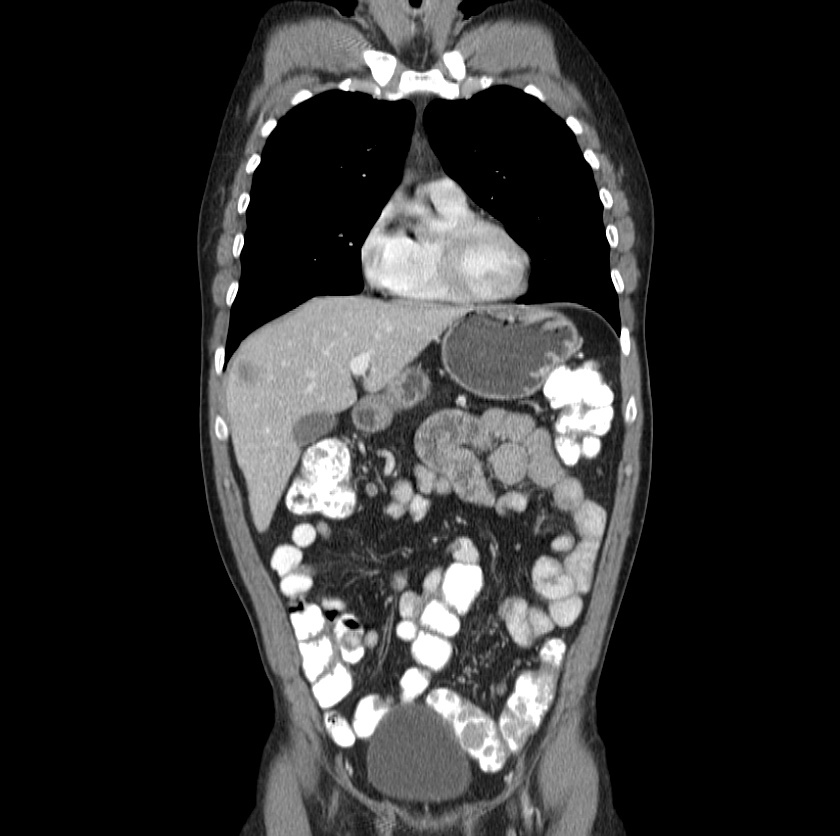

The liver was the most frequent site of involvement in our study (74.8% of cases). Of the 275 patients with liver involvement, 133 (48.3%) had isolated liver involvement, 74 (26.9%) had concomitant liver and lung involvement, and 68 (24.7%) had concomitant involvement of the liver and of organs other than the lung (,Table).

The second most common site of involvement in our series was the lung (n = 89 [24%]). Seventy-four of these 89 cases (83.1%) demonstrated isolated lung involvement. Other sites of involvement (in decreasing order of frequency) included the peritoneum, kidney, brain, mediastinum, heart, bone, soft tissues, spinal cord, spleen, pleura, adrenal glands, bladder, ovary, scrotum, and thyroid gland (,Table). Ovarian and thyroid gland involvement in our study were not systemic, whereas bladder and scrotum involvement were concomitant with liver and peritoneal disease.

Hydatid disease

Hydatid cysts result from infection by the Echinococcus tapeworm species and can result in cyst formation anywhere in the body.

Location

hepatic hydatid infection: most common organ (76% of cases) 1,5

pulmonary hydatid infection: second most common organ (15% of cases)

splenic hydatid infection: third most common organ (5% of cases) 8